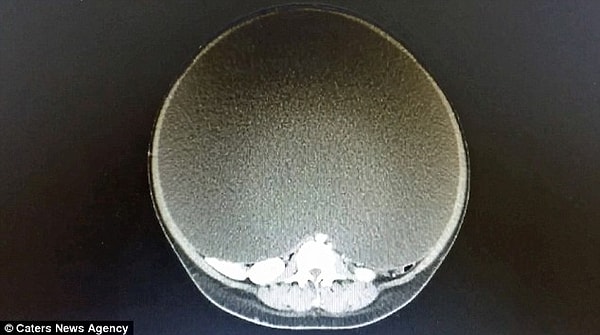

5. Это рентгеновский снимок кисты яичника этой женщины

«Я впервые оперировал кисту таких размеров. В диаметре она была около полуметра, а ее обхват составлял 157 см. Исходя из тех исследований, что я просмотрел, это самая большая киста в истории медицины, которую удалось извлечь, не выкачивая при этом из нее жидкости».